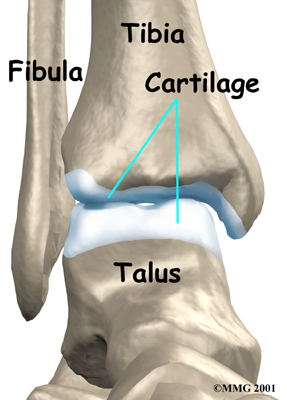

The ankle joint is made up of three bones: the lower end of the tibia (shinbone), the fibula (the small bone of the lower leg), and the talus (the bone that fits into the socket formed by the tibia and fibula). The talus sits on top of the calcaneus (the heelbone).

Inside the joint, the bones are covered with a slick material called articular cartilage. Articular cartilage is the material that allows the bones to move smoothly against one another in the joints of the body.

Articular Cartilage

The cartilage lining is about one-quarter of an inch thick in most joints that carry body weight, such as the ankle, hip, or knee. It is soft enough to allow for shock absorption but tough enough to last a lifetime, as long as it is not injured.